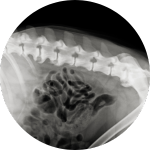

Der Begriff Dysplasie stammt aus dem Griechischen und bedeutet „schlechte Form“. Hüftdysplasie beim Hund – auch HD abgekürzt – und Ellbogendysplasie - auch ED abgekürzt - ist eine Erkrankung der Hüftgelenke, die zumeist erblich bedingte Ursachen hat und leider ziemlich häufig vorkommt. Aufgrund ihres Körperbaus sind große Hunderassen wie Schäferhunde, Retriever oder Boxer besonders oft von einer Hüftdysplasie betroffen.

Das Ausmaß der Beschwerden einer HD kann bei Hunden je nach Alter und Schweregrad der Hüftgelenksdysplasie unterschiedlich ausfallen. Die Hüftprobleme von betroffenen Hunden können allerdings mit dem Alter stärker werden, falls keine geeignete tierärztliche Diagnose und Behandlung erfolgen.

Eine fortgeschrittene Hüftdysplasie kann bei Hunden sogar zu einer Arthrose an der Hüfte führen.